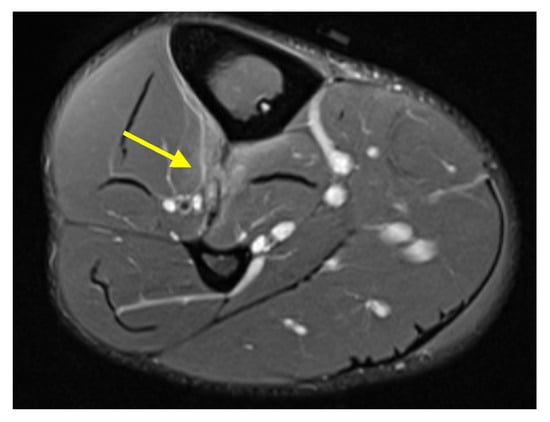

The IOM can be evaluated by a variety of modalities including ultrasound, CT, and MRI. On all modalities, a normal IOM appears as a thin and continuous membranous structure extending between the tibia and fibula. On MRI, the normal IOM is thin and hypointense in all sequences and extends from the proximal tibiofibular joint to the distal tibiofibular syndesmosis (Figure 4). The anterior tibialis and posterior tibialis muscles have broad attachments on the anterior and posterior aspects of the IOM, respectively.

Figure 4. Normal comparison. (a) Axial proton density fat saturated MR image and (b) axial T1-weighted MR image demonstrate a normal MRI appearance of an intact IOM (yellow arrow and brackets) at the level of the mid tibia–fibula.